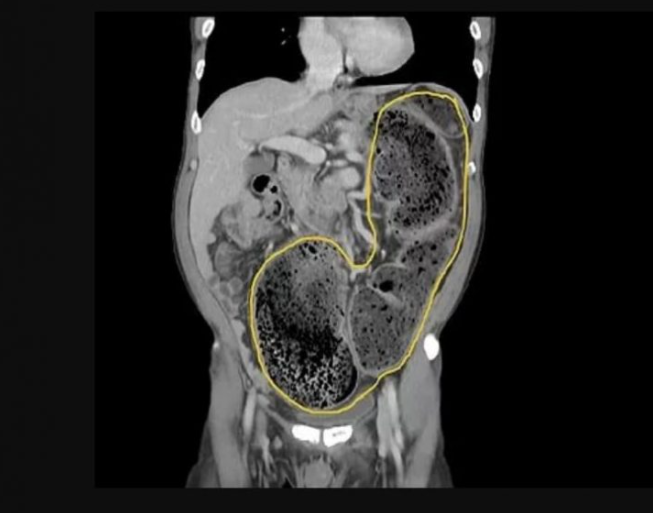

20일이 지나도 변을 보지 못해 심장 앞까지 변비가 꽉 찬 남성의 CT 사진이 올라와 보는 이들에게 엄청난 충격을 주고 있다.

최근 중국 의과대학 신주부속병원 페이스북 계정에 58세 남성 A씨가 20일 넘게 변을 보지 못해 이 병원 응급실로 실려갔다.

대장직장외과 전문의인 장주헝 박사가 이 남성을 진찰한 결과 장에는 배출하지 못한 변들이 모여 딱딱하게 굳어 장폐색이 온 상태라고 전했다.

특히 장 끝부분 S상 결장에 변이 계속해서 차올라 거의 심장까지 올라가 있어 모든 의료진들이 놀라움과 충격을 받았다.

더욱 더 놀라운 것은 장에 꽉 찬 변의 무게만 5kg가 넘었다.